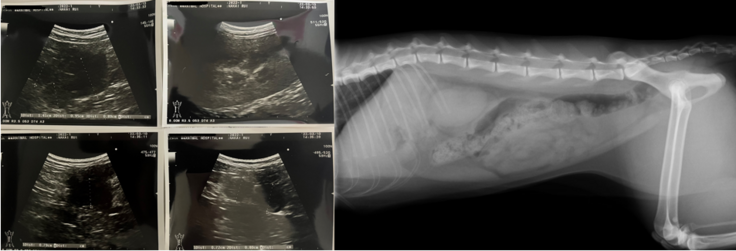

超音波検査、X線検査、細胞検査(外部機関)を実施する。

・超音波検査の画像上、腹腔内に病変あり

・細胞検査に数日かかる